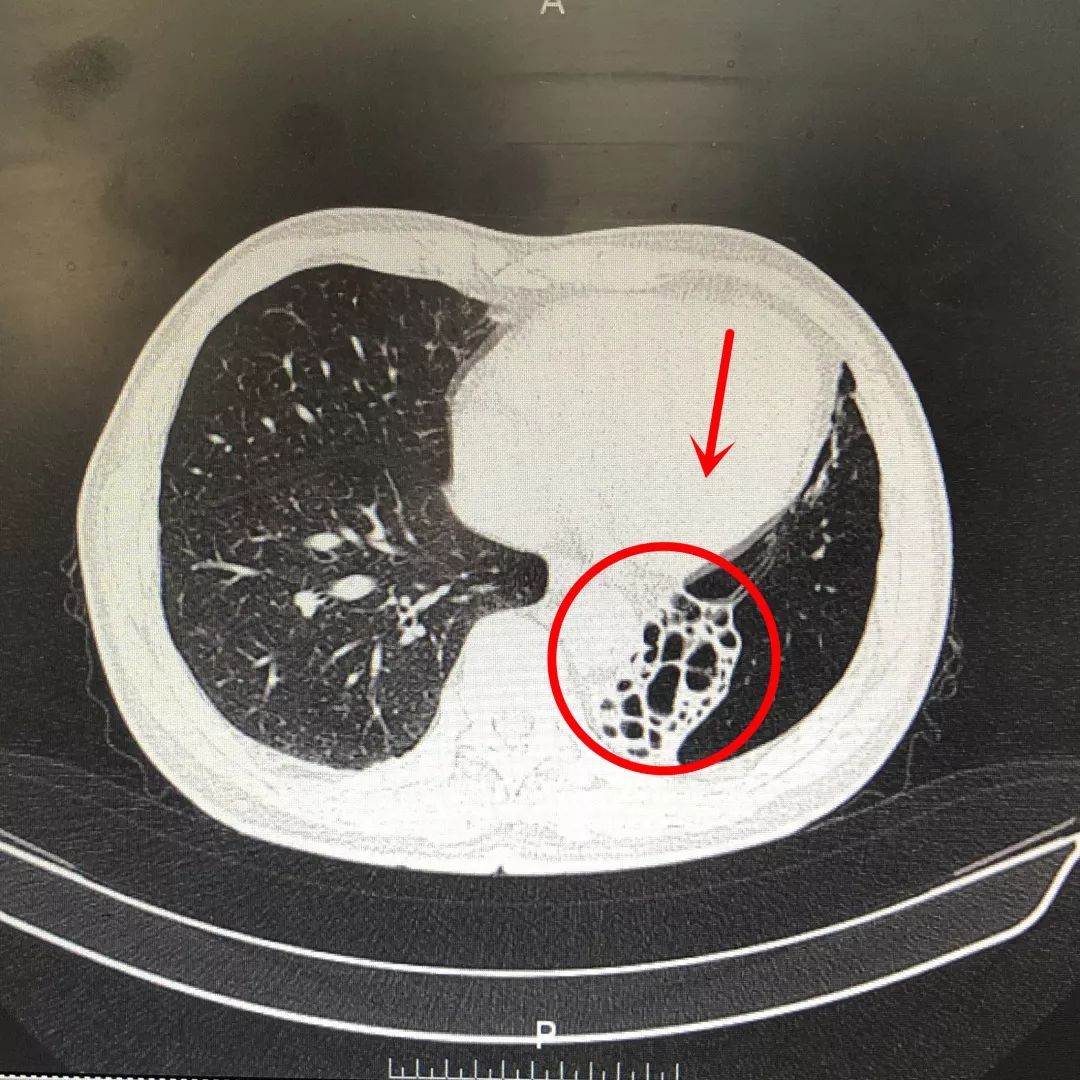

左肺积满了脓痰却咳不出一口痰真相竟是

6年反复咳嗽的病因终于找到了

泉州一男子咳嗽2年,伴有脓痰和血丝!